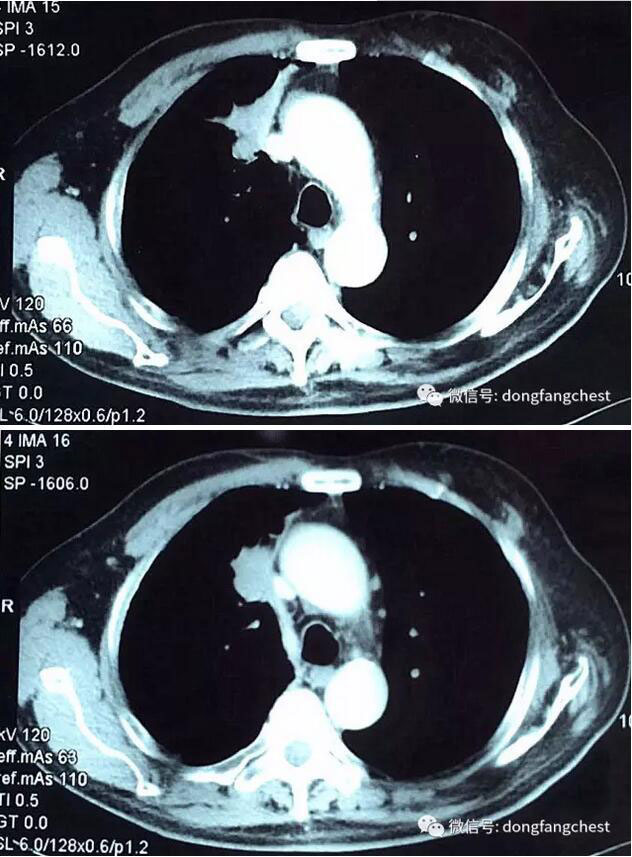

由于肿瘤体积较大,且与肺动脉、上腔静脉关系紧密,手术实施起来较为困难,经过东方总院多学科讨论会诊,决定先于呼吸内科进行了2个疗程新辅助化疗。

化疗后,李老体内的肿瘤体积明显缩小,随后于2月22日进入总院心胸外科进行手术治疗。手术由总院胸外科朱胜主任、王鸿副主任、高涛涛医生共同完成。术中发现肿瘤侵犯右肺动脉干、上腔静脉部分血管壁。术中,经上腔静脉远端、右心房插管转流,阻断受肿瘤侵犯部位腔静脉后予以部分血管壁切除,然后取心包组织进行上腔静脉修补重建。